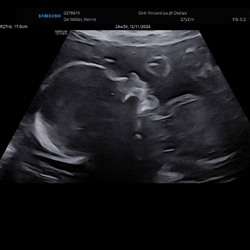

Heel herkenbaar. Vrijdag 10 weken zwanger en paniekeer bij het kleinste. Eerste echo gehad bij 7 weken

Vorige keer is het misgelopen op 6 weken, nu en ik 12 weken. Vooral als mijn symptomen minderen, word ik zo ongerust. Nu ben ik wel net in de termijn dat dit normaal is en ik kan het hierdoor ook wat meer loslaten.

Ik merk dat ik me wel steeds geruster voel na elke echo (heb er nu 2 gehad).